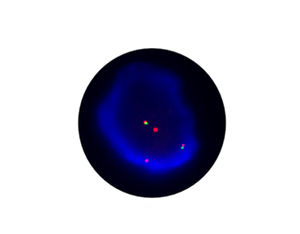

- FISH

1.非小細胞肺がんでは、inv (2) (P21; P23)が融合遺伝子EML4-ALKの分子サブユニットを形成し、標的薬Crizotinibのターゲットとなっています。

2.2010年の非小細胞肺がん診療ガイドラインでは、ALK阻害剤の効果予測のために、新たにEML4-ALKの評価項目が追加されました。